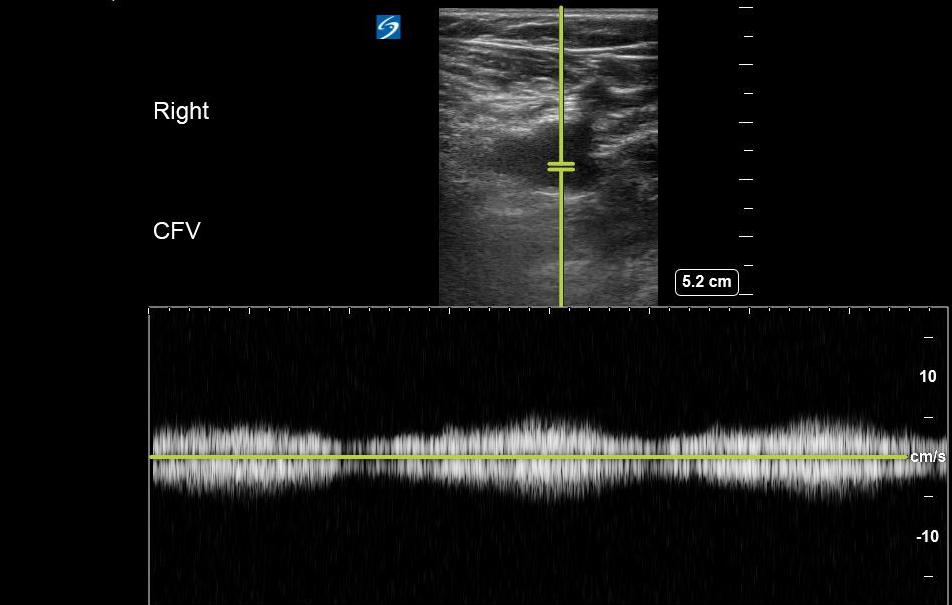

- Involves placing the transducer on the leg, typically at the CFV, and setting the ultrasound machine to spectral (pulsed wave) Doppler mode.

- Flow velocity in deep venous structures varies with the respiratory cycle and changes in intrathoracic pressure.

- A lack of variation in flow may be suggestive of an obstructive process (eg, thrombus, compressive pathology) along the venous system between the proximal inferior vena cava and point of transducer placement. (Figure 17)

- Figure 17. Respiratory variation seen at the CFV with Pulsed wave Doppler.